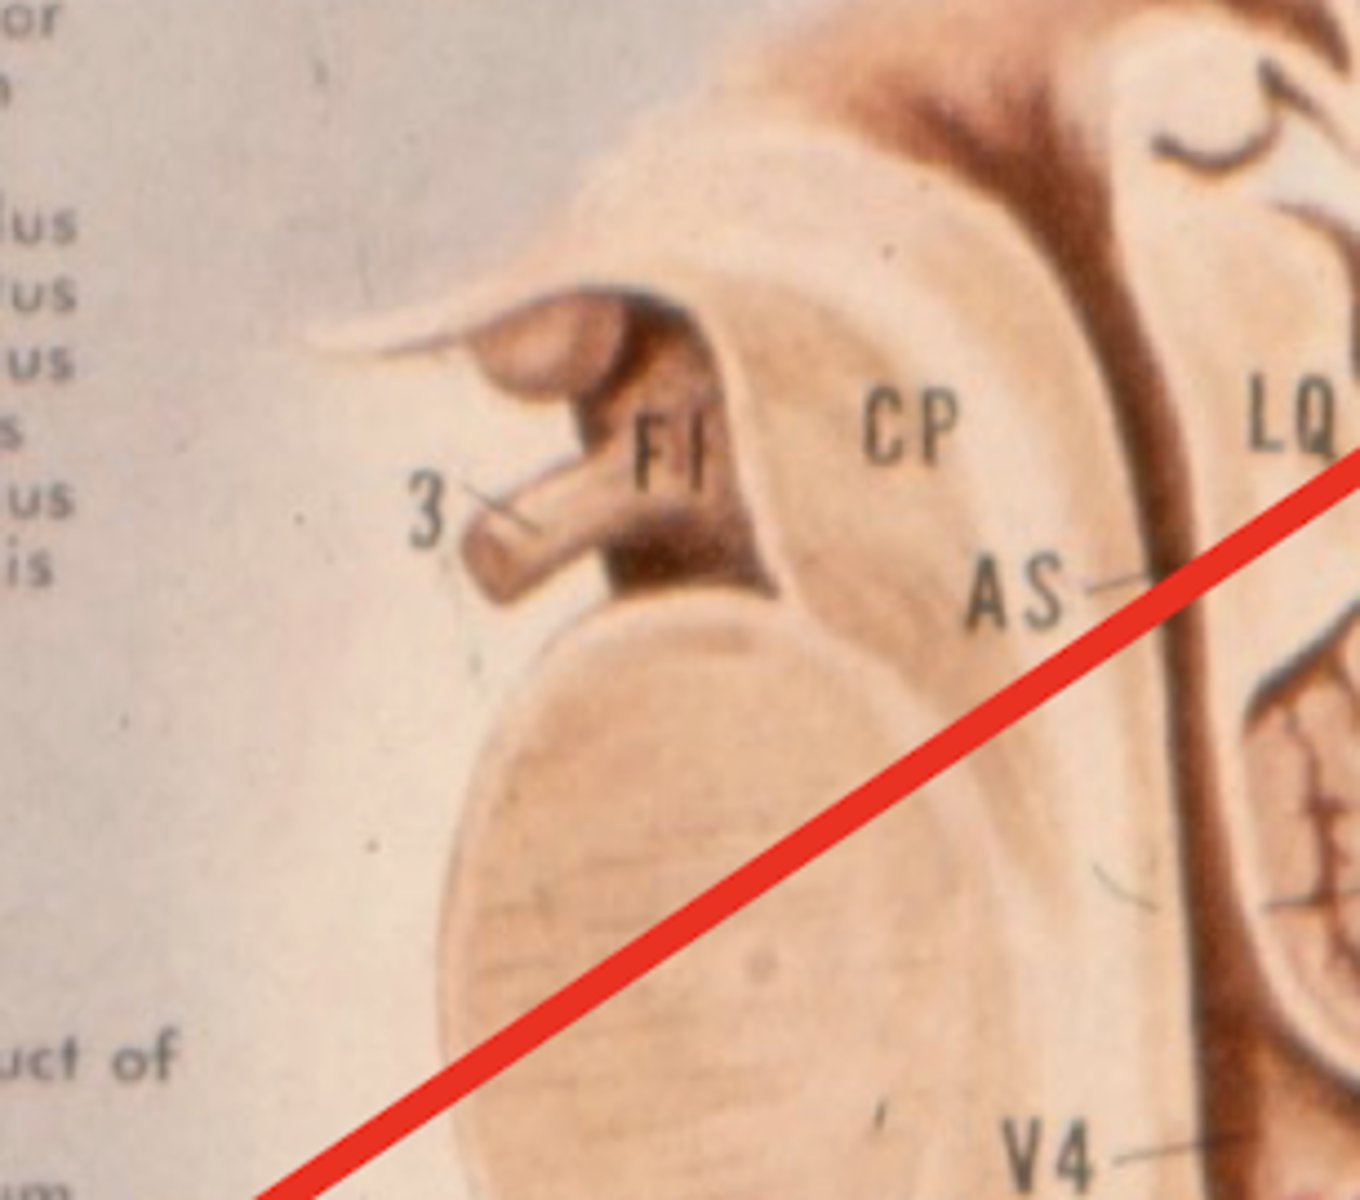

image -- 5

What other notable structure should you see if you see two red nuclei?

"if you see two red nuclei you're at the superior colliculus level"